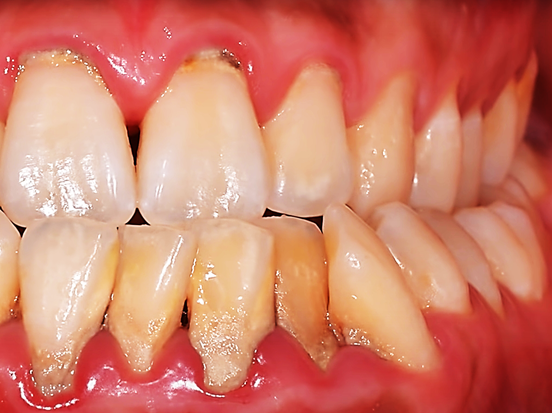

치석은 잇몸질환의 가장 근본적인 원인이고 첫 번째 원인이 됩니다.

치석 표면은 거칠어서 프라그가 쉽게 붙을 수 있는 장소가 됩니다.

프라그는 세균덩어리입니다. 잇몸질환을 유발하는 주된 원인이기 때문에 프라그가 잘 생길 수 있는 치석을 제거하는 관리는 꼭 필요합니다.

잇몸과 치아 경계에 치석이 생기면 염증이 생기기 쉽고 이로 인해 잇몸이 민감해져 혈관이 확장되어 통증과 출혈이 생길 수 있습니다.

스케일링 후에 치아 사이 공간 ‘블랙 트라이앵글’이 보이기도 하는데 이것은 그동안 잇몸병이 진행되어 부었던 것이 가라앉으면서 생긴 흔적입니다.